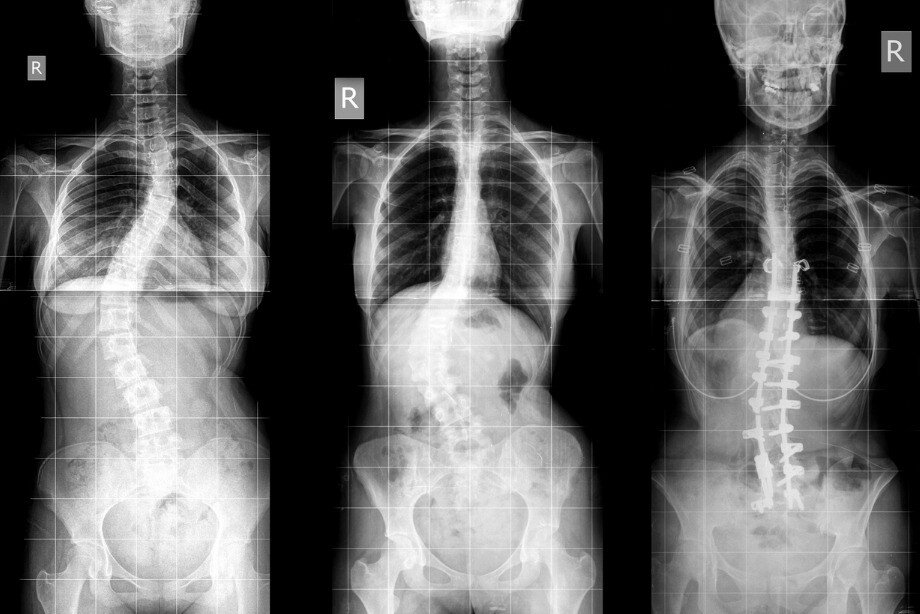

Что делать, если появились признаки нарушения осанки? Для начала следует дать определение двум самым распространённым состояниям, которые чаще всего путают. Нарушение осанки – это устойчивое отклонение туловища от нормального положения. Это состояние можно назвать предвестником болезни, поскольку оно существенно увеличивает вероятность развития целого ряда заболеваний опорно-двигательного аппарата. Сколиоз – это заболевание опорно-двигательного аппарата, характеризующееся искривлением позвоночника во фронтальной (боковой) плоскости с разворотом позвонков вокруг своей оси и ведущее к нарушению функции грудной клетки.

Для начала следует дать определение двум самым распространённым состояниям, которые чаще всего путают. Нарушение осанки – это устойчивое отклонение туловища от нормального положения. Это состояние можно назвать предвестником болезни, поскольку оно существенно увеличивает вероятность развития целого ряда заболеваний опорно-двигательного аппарата. Сколиоз – это заболевание опорно-двигательного аппарата, характеризующееся искривлением позвоночника во фронтальной (боковой) плоскости с разворотом позвонков вокруг своей оси и ведущее к нарушению функции грудной клетки.

«Нарушение осанки на ранней стадии может определить специалист в ходе визуального осмотра. Если мы говорим о детском возрасте, то ежегодный осмотр позволяет на ранней стадии определить «зарождающийся» сколиоз», — поделилась с «Чемпионатом» спортивный врач Crocus Fitness Дана Гудкова. Делаем вывод: любую проблему лучше всего решать в детском возрасте, так как это наиболее быстро и эффективно. Но это не значит, что взрослый человек должен бездействовать. Даже в зрелом возрасте можно если не исправить полностью, то значительно подкорректировать проблемы с осанкой.